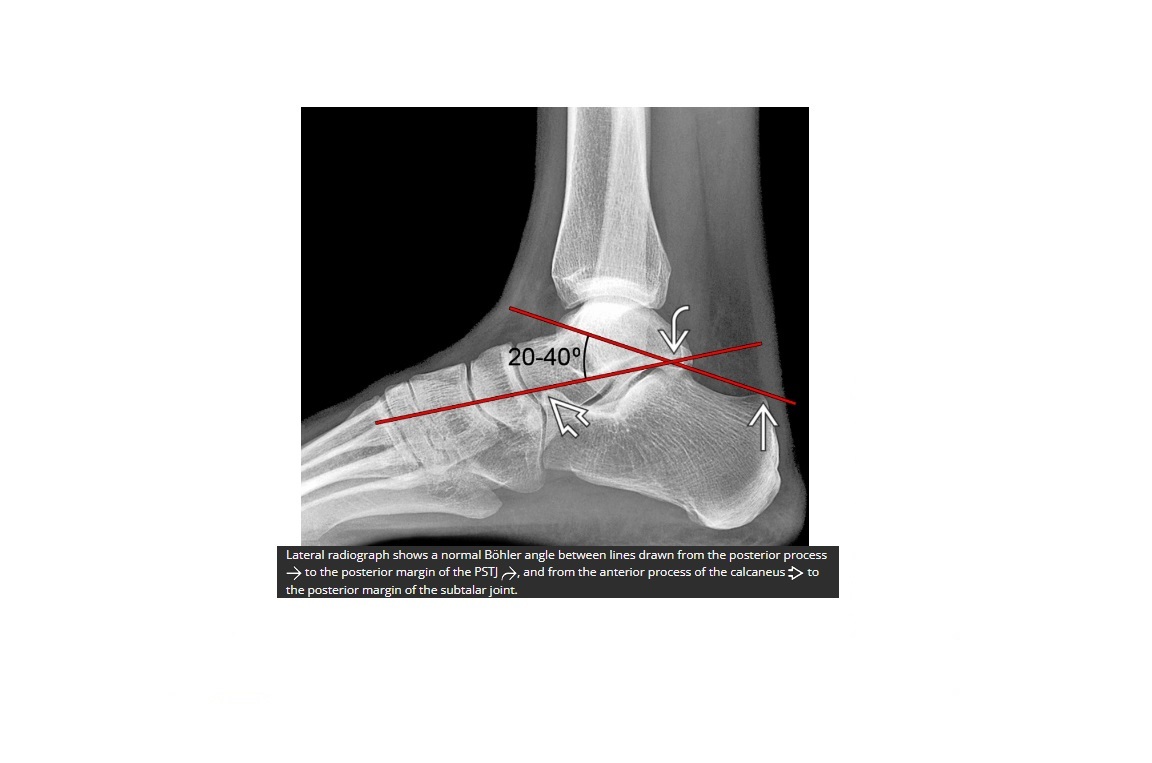

What is bohlers line?

A

line drawn between the anterior and posterior borders of the calcaneus

< 20 ? fracture